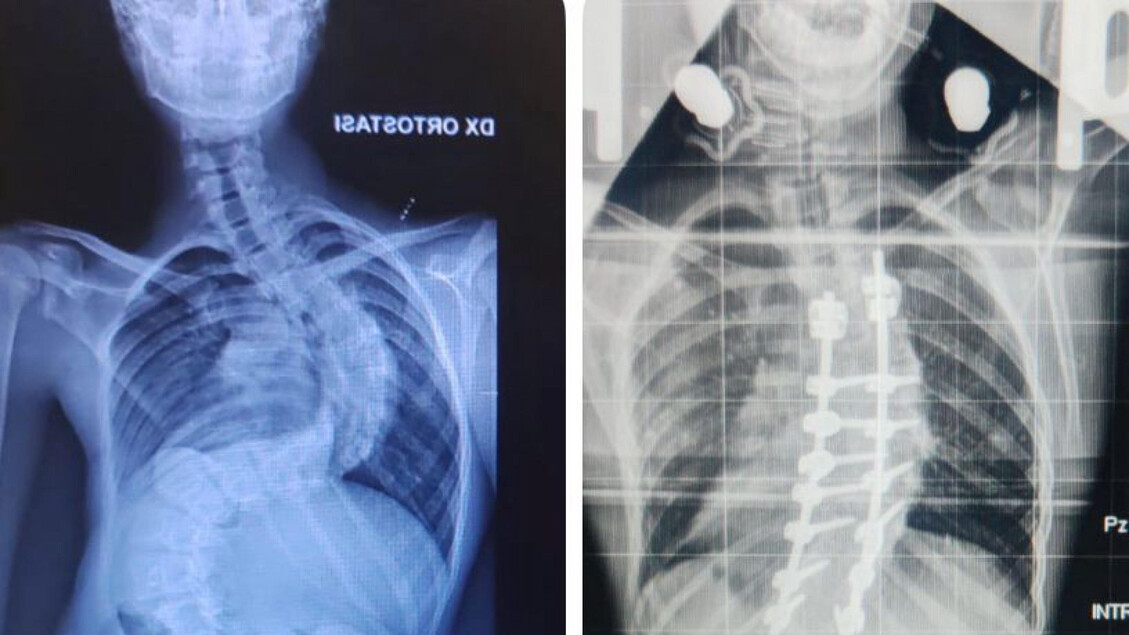

Francesco, come spiegato dal dottor Piazzolla, presentava una forma di scoliosi particolarmente aggressiva, con un peggioramento di oltre 30 gradi in soli tre mesi. Questa rapida evoluzione ha reso necessaria una preparazione preoperatoria complessa e dettagliata. Durante il suo soggiorno in ospedale, che ha incluso la celebrazione del suo compleanno, il ragazzo รจ stato sottoposto a una trazione continua mediante un dispositivo speciale chiamato halo. Questo strumento รจ stato fondamentale per preparare progressivamente la colonna vertebrale all’intervento chirurgico, consentendo ai medici di ridurre la curvatura della scoliosi a 45 gradi.

Il dottor Piazzolla ha evidenziato lโimportanza di una preparazione accurata e del supporto continuo, che hanno permesso di affrontare un intervento cosรฌ delicato. La chirurgia vertebrale del Policlinico di Bari si รจ dimostrata all’avanguardia, non solo per la qualitร delle operazioni, ma anche per lโumanitร dimostrata nei confronti dei pazienti e delle loro famiglie.